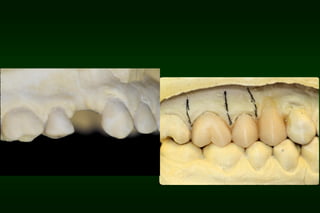

Types of Provisional Restoration II.Customized resin restorations 2. Indirect technique • • Initial and final polymerizations occur extraorally The first step is preparing a index (e.g. vacuum shell) on study cast prior to tooth preparation visit

Types of Provisional Restoration II.Customized resin restorations 2. Indirect technique Advantages: 1. Improved marginal accuracy 2. Prevention of pulpal and soft tissue irritation 3. Reduced chair time 4. More comfortable for patient

Types of Provisional Restoration II.Customized resin restorations 2. Indirect technique Disadvantages: 1. Laboratory procedure required 2. Dental auxiliary required